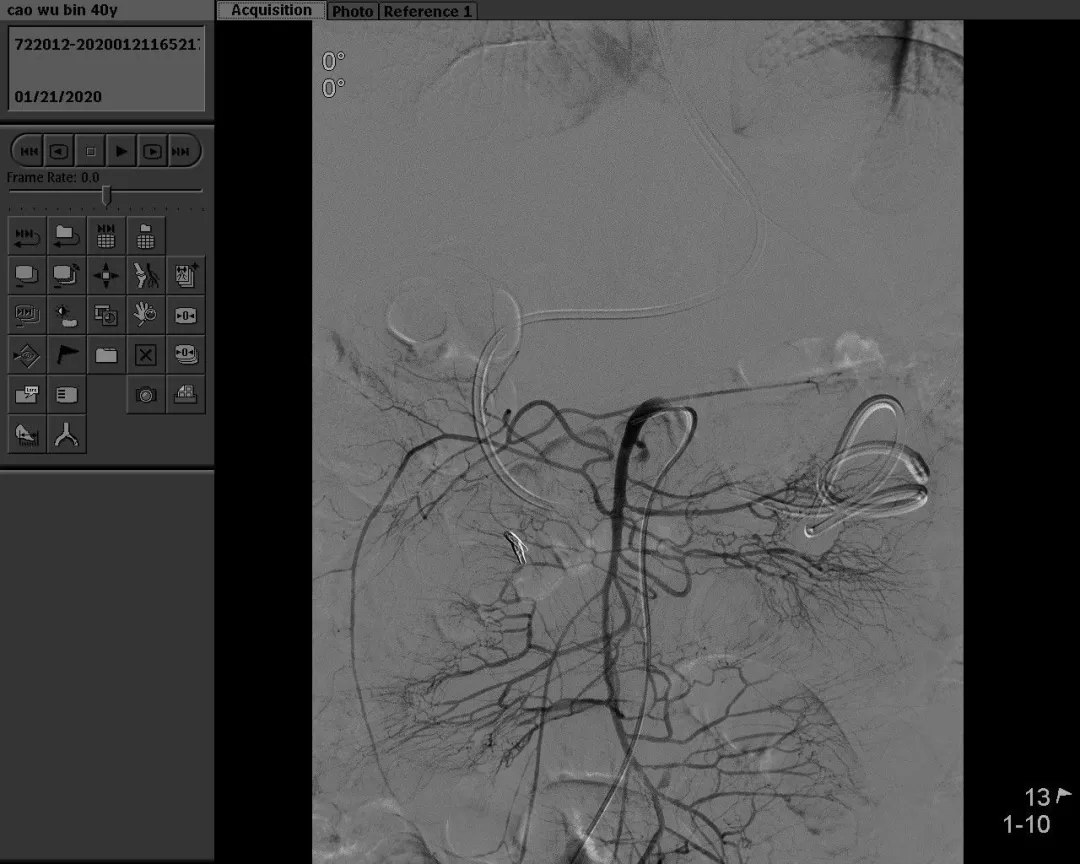

病例三:男,解暗红色血便10余天,外院胃肠镜无明显出血灶,以“消化道出血”收治住院。

South Africa red wine

急诊DSA示:空肠动脉分支出血,予空肠动脉栓塞术。